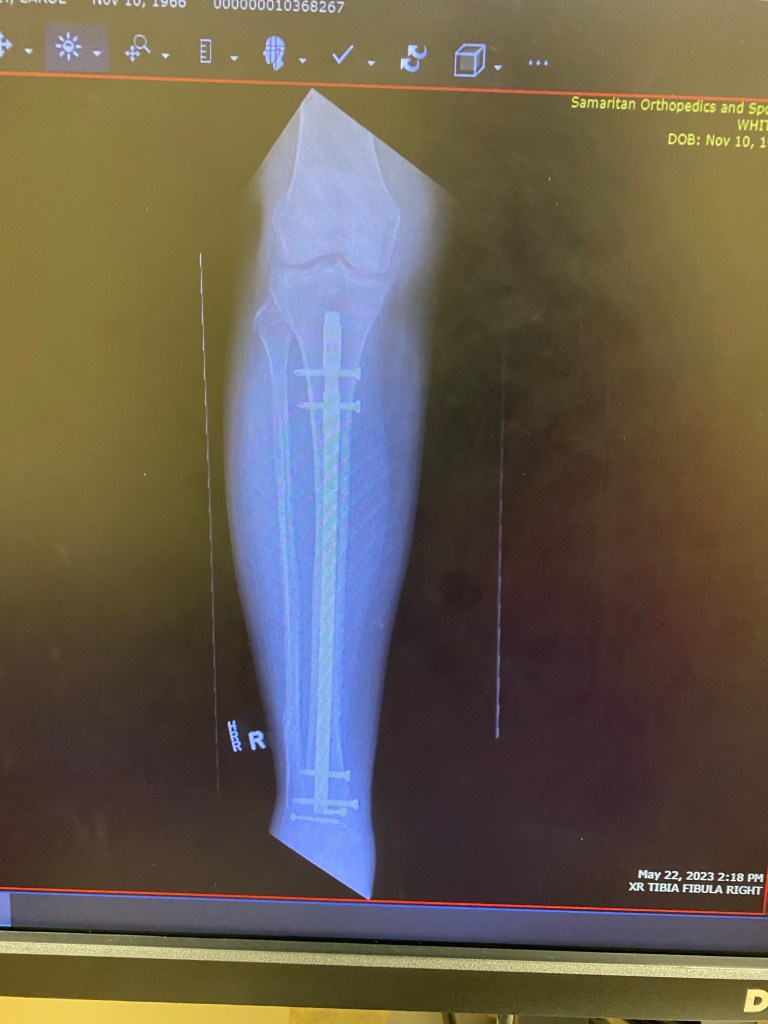

For the surgery they gave me two nerve blockers for the pain of the procedure. Six pins and a rod were inserted from above my knee since the bones were in half. My surgeon monitored the leg from an X-ray during the surgery. I was on non weight bearing for a month and a half. The last month of that I was in a nursing home.